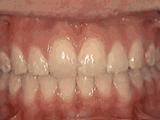

9、牙列稀疏,个别牙齿反合,对刃咬合容易造成牙齿损伤或过度磨耗牙釉质,经过矫正后的是这样的~

10、深覆盖,咬合时,下前牙咬在上牙内侧牙肉上,容易造成牙齿和牙肉损伤,咬合功能差,经过矫正后的牙齿是这样的~

看完上面动图,是不是觉得很直观?看了这些图想要矫正的朋友是不是就安心了?当然,由于每个人的具体情况不同,所以还是要听从专业的正畸医生的建议